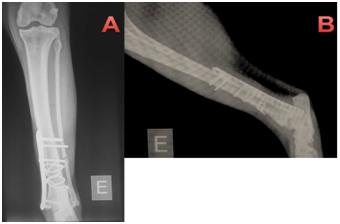

Immediate post-operative radiographs were taken in cat 1 (Figure 3) and 2 (Figure 4), with follow-up radiographs at 21days and 42days post-surgery. The cats were discharged the day after surgery, and re-examined for suture removal after 10days. Cephalexin (30mg/kg every 12hours for 7days orally), meloxicam (0.05mg/kg every 24hours for 3days orally), dipyrone (25mg/kg every 24hours for 5days, orally), tramadol hydrochloride 2mg/kg every 12hours for 5days, orally) were prescribed post-operatively and a protective collar was dispensed to prevent the removal of the stitches. After 10days, the animals returned to HV-UFPR for removal of the stitches and orthopedic evaluation. Immediate post-operative radiographs showed excellent apposition and alignment of bone fragments. Plates were well positioned and fracture lines were not visible (Figure 2). The alignment, fragment fixation, apparatus placement and biological activity were good. The fracture line was not visible, thus showing compression of the fragments using cerclage. The plates have neutral function in both cases, therefore clerk as primary tutor and board as secondary tutor.

Figure 3 Immediate post-operative osteosynthesis of the left tibia of cat 1.

1. Craniocaudal projection in which two cerclage wires were seen to cause compression of the bone fragments (fracture line not visible) and neutral blocked plate, using two screws locked in the distal fragment and three in proximal fragment. Fibular fracture, without implants.

2. Lateral-medial projection showing the same apparatuses as in A, note fracture line not visible.